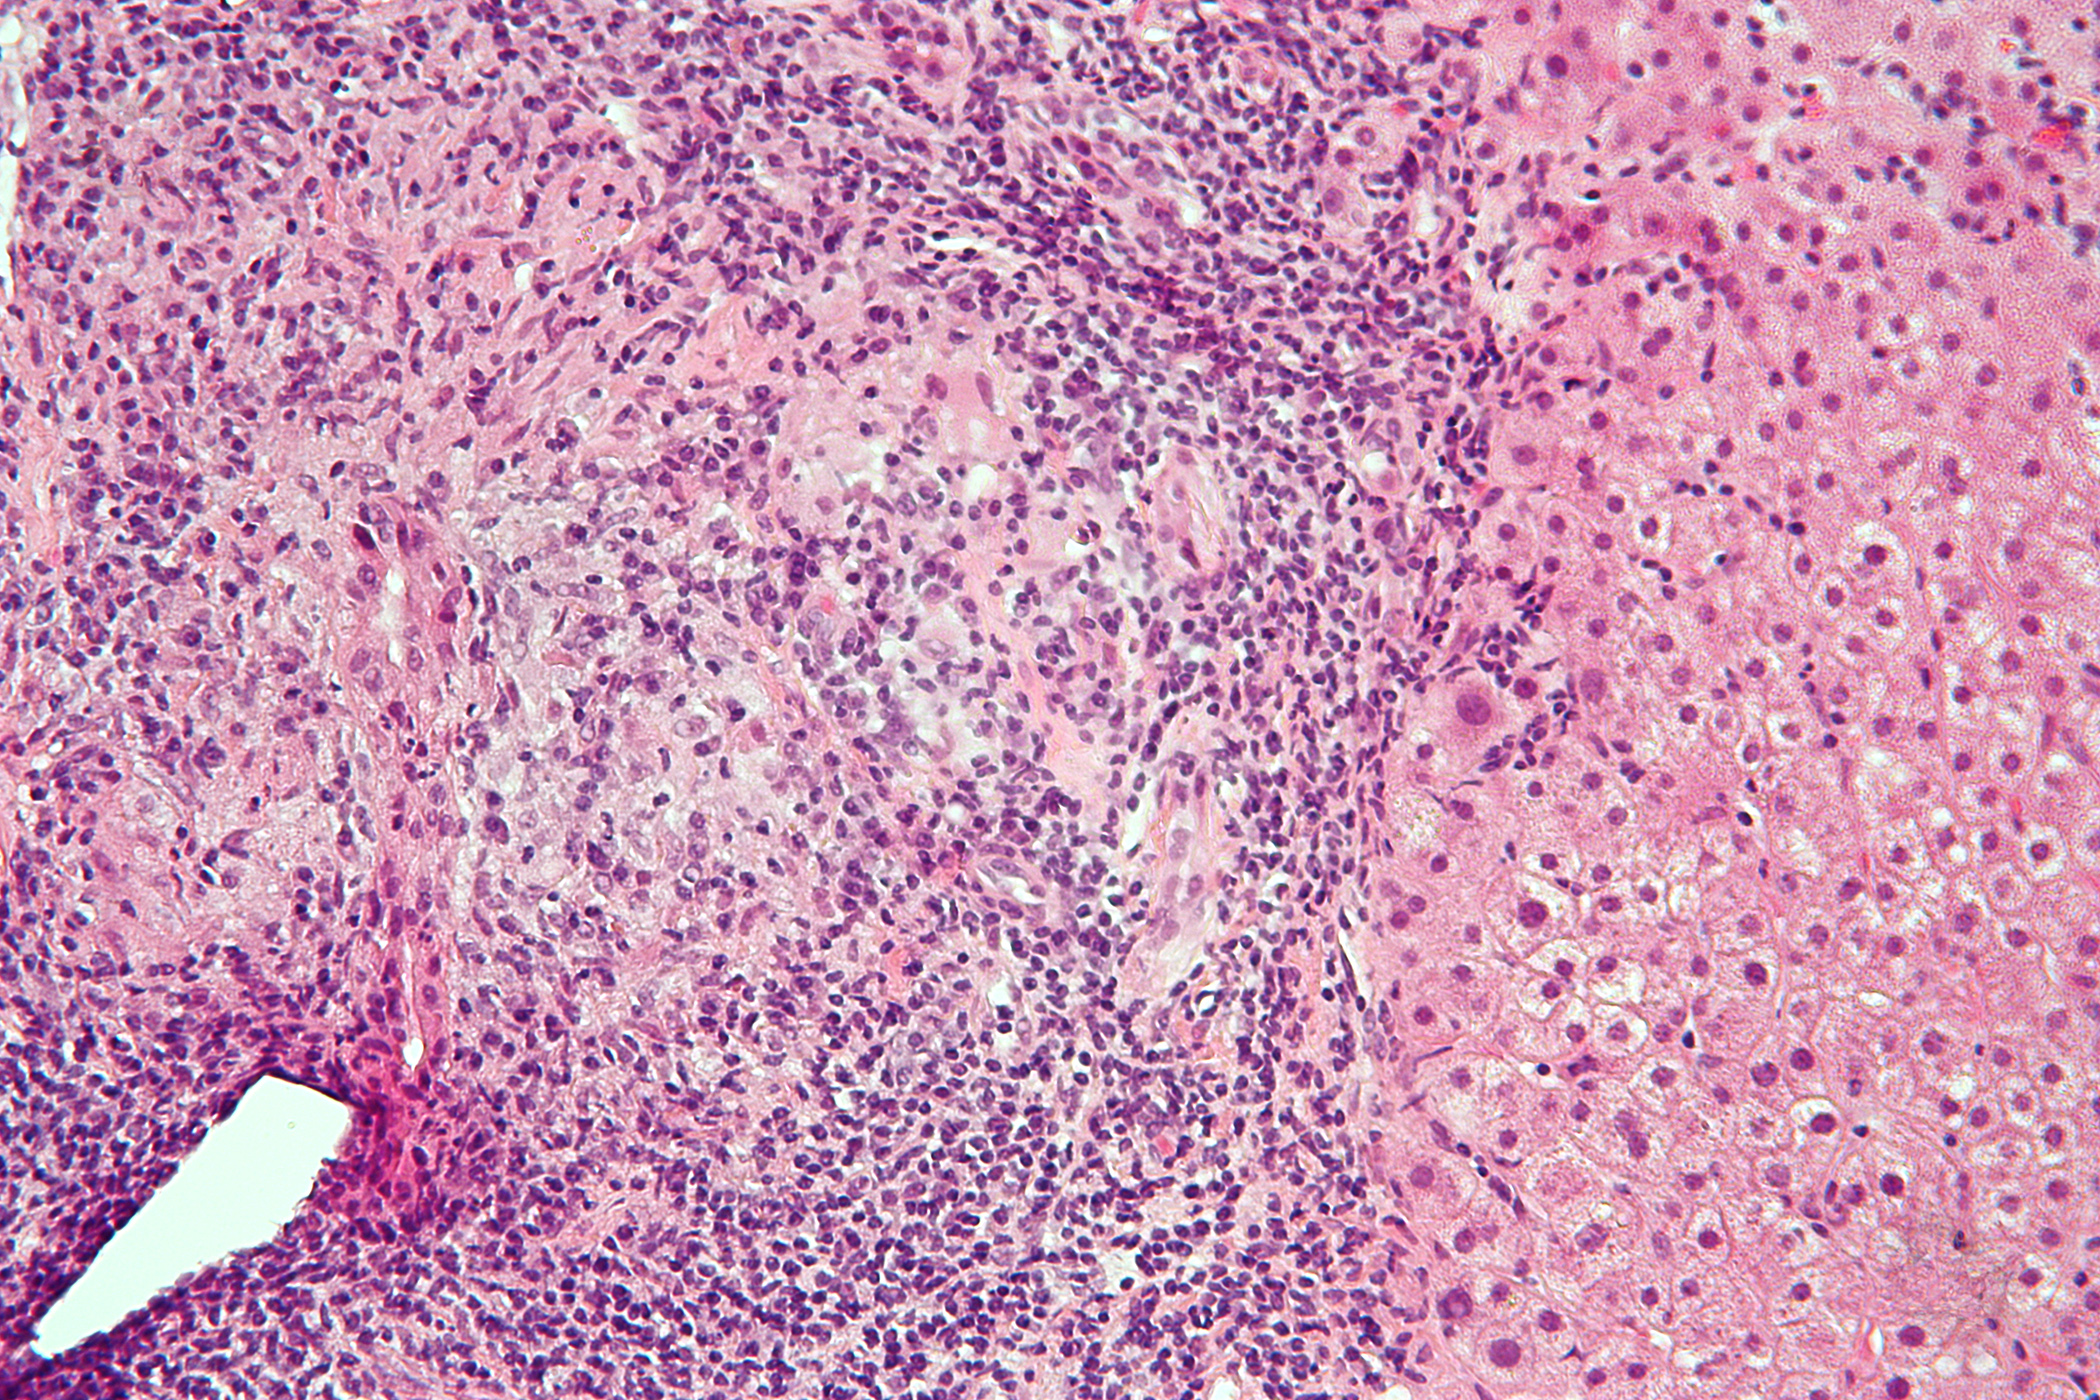

Der Vortrag eines renommierten kanadischen Onkologen zu vielversprechenden Heilungsmöglichkeiten bei Darmkrebs durch Bewegungstherapie sorgte für Aufsehen auf der diesjährigen ASCO. Die im Rahmen dieses Vortrags vorgestellten Ergebnisse einer randomisierten kontrollierten Phase-III-Studie belegen, dass ein strukturiertes Bewegungsprogramm nach der Chemotherapie das krankheitsfreie Überleben von Darmkrebspatienten in signifikanter Weise verlängern kann.